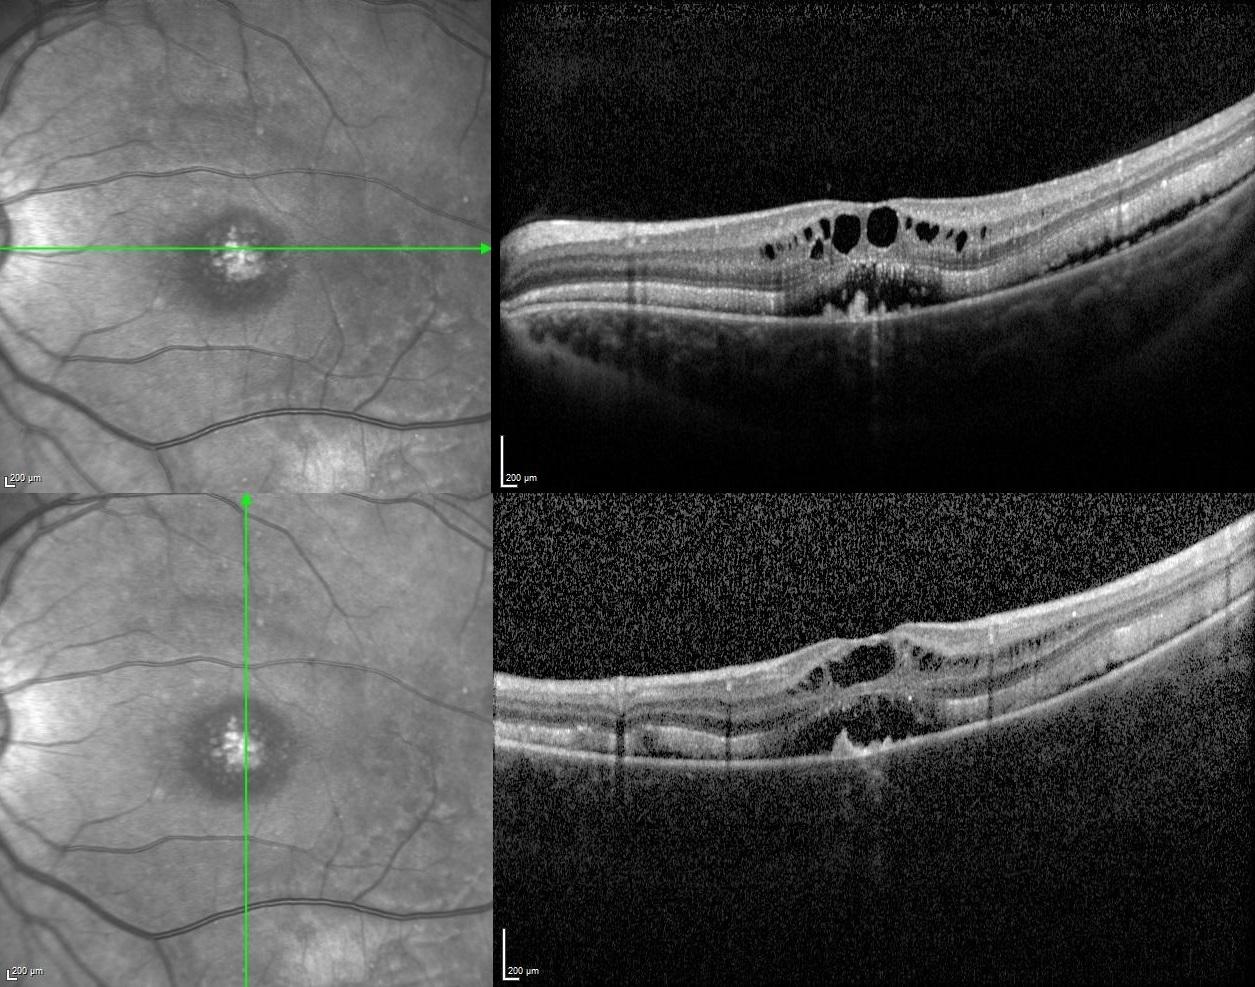

Vertical and horizontal optical coherence tomography scans passing through the fovea revealed serous retinal detachment, retinoschisis with intraretinal cysts, brush border appearance caused by elongation of the outer segments of photoreceptors, and hyperreflective dome-shaped deposits at the level of retinal pigment epithelium in both eyes.

According to the multimodal imaging characteristics, the preliminary diagnosis was ARB and electrooculogram (EOG) was performed to confirm the diagnosis. EOG showed the absence of light rise in which Arden ratios were detected as 1.46 in the right and 1.51 in the left eye. For the definitive diagnosis, genetic analysis was performed and compound heterozygous mutation in BEST1 gene was detected.